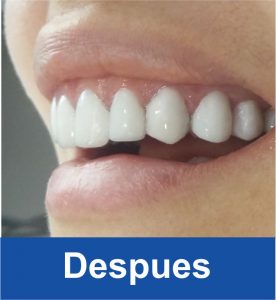

Diseño de Sonrisa

Despues

Despues